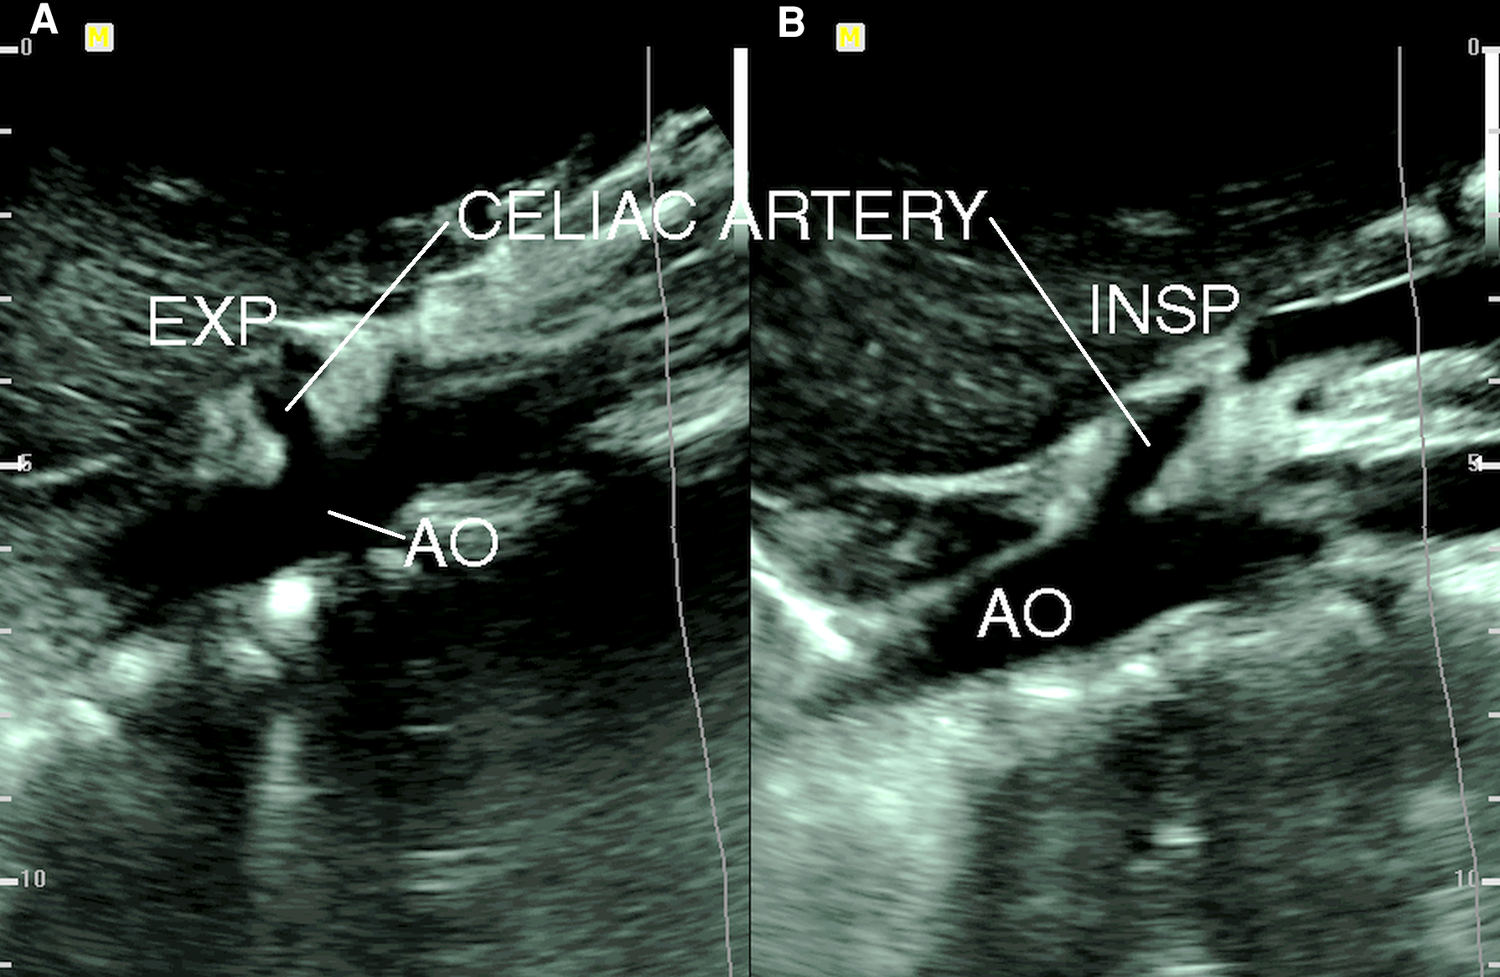

Gruber and colleagues (16) compared the findings of duplex ultrasound in six patients with CACS with 20 age-matched asymptomatic volunteers and found that a peak systolic velocity (PSV) of the CA during expiration greater than 350 cm/s had an 83% positive predictive value (PPV) and a 95% negative predictive value (NPV). The CA deflection angle (end-expiratory upturn angle) of 50° or more has a PPV of 43% and an NPV of 100%, and the combination of CA PSV (>350 cm/s) and deflection angle (>50°) has a PPV of 100% and NPV of 95%. Saleem and coauthors (17) described the ultrasound criteria that are supportive in diagnosing CACS, which include expiratory CA PSV of > 200 cm/s and a CA deflection angle of > 50°. The changes of CA deflection angle during inspiration and expiration in a patient with CACS are shown in Figure 2. Another ultrasound criterion for diagnosing CACS includes measuring the PSV of the CA during the expiratory phase. A PSV of over 200 cm/s or a ratio of PSV of CA to aorta of greater than 3:1 in the expiratory phase can also indicate CACS (18–23). In patients with an optimal sonographic window, the “hook” or “J” shape of the proximal CA caused by extrinsic compression by the MAL can be demonstrated in the sagittal plane with a B-mode or color Doppler imaging (24).

Figure 2

B-mode ultrasound image of celiac artery compression. (A) Celiac artery deflection angle > 50° during expiration (EXP); (B) celiac artery deflection angle < 50° during inspiration (INSP). AO, aorta [from: Youssef (18). Reprint with permission from Dr Youssef].